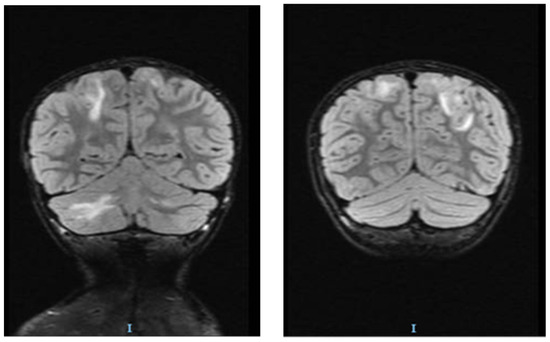

2. Case Report